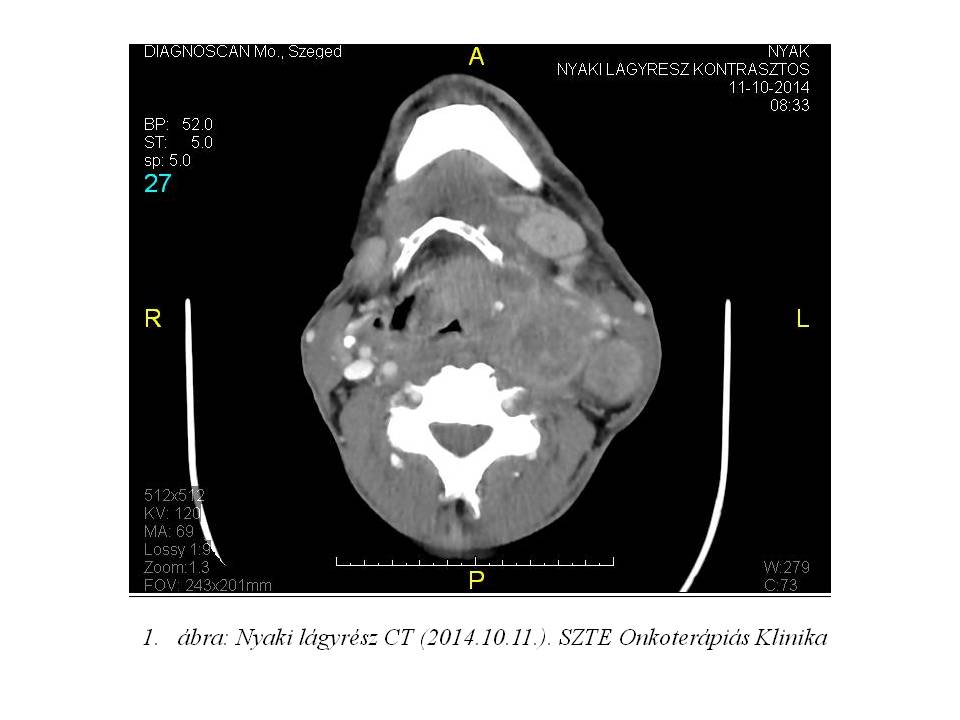

Multidiszciplináris team (fül-orr-gégész, onkológus, sugárterapeuta) döntése alapján indukciós TPF (Docetaxel, Cisplatin, 5-FU) kemoterápia nem jött szóba a beteg igen gyenge általános állapota miatt. Definitív kemo-radioterápiát kezdtünk (2. ábra: TCT, Besugárzás tervezés), azonban intermittálóan jelentkező, convulsiv, flexiós tónusos görcsökkel járó rosszullétek miatt SBO-ra került, kezelését nem tudtuk folytatni. Ezt követően neurológián obszerválták, epilepszia irányába további vizsgálatok történtek. EEG epilepsziát nem igazolt, a convulsiv rosszullétek hátterében hypoxiás epizódokat véleményeztek. A hypoxiát a nagy kiterjedésű nyaki nyirokcsomó konglomerátum általi carotis sinus baroreceptor kompresszió okozhatta.